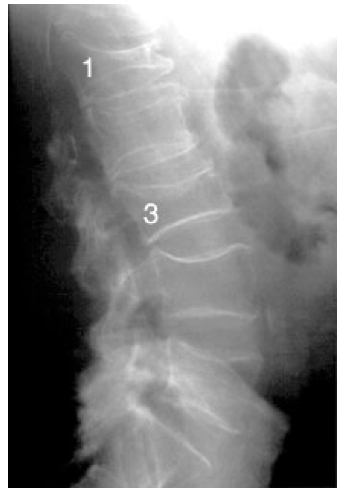

Vertebral body compression:

Accumulation of vertebral body fractures can cause progressive kyphosis of the thoracic spine (Dowager’s hump), respiratory compromise, restrictive lung disease, and an increased risk of pneumonia..

_..X-ray imaging reveals thickened bone cortex with shaggy radiolucent lytic lesions interspersed throughout the bone matrix. Bone with these features are described as having a cotton wool appearance.

“Chalk-stick fractures” are fractures, typically of long bones, in which the fracture is transverse to the long axis of the bone, like a broken stick of chalk. Commonly seen in Paget’s disease of bone and osteopetrosis.